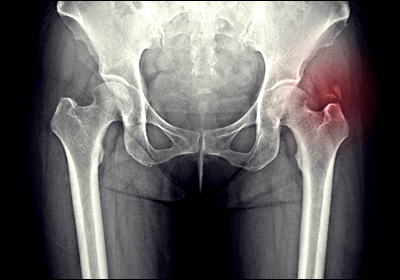

고관절 통증의 진단 방법

고관절 통증의 정확한 진단을 위해서는 여러 가지 방법이 사용됩니다. 먼저 의사와의 상담을 통해 증상의 양상, 지속 기간, 악화 요인 등을 자세히 파악합니다. 이어서 신체 검사를 통해 관절의 움직임, 압통 여부, 근력 등을 평가합니다. X-ray는 관절의 구조적 변화를 확인하는 데 유용하며, 관절염이나 골절 등을 진단하는 데 도움이 됩니다. 더 자세한 관찰이 필요한 경우 MRI나 CT 스캔을 실시할 수 있습니다. 이를 통해 연골, 인대, 근육 등 연부조직의 상태를 확인할 수 있습니다. 때로는 혈액 검사를 통해 염증 수치를 확인하거나, 관절액 검사를 통해 감염이나 결정성 관절염 등을 진단하기도 합니다.